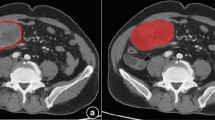

Tumor segmentation

Lesions were delineated on the CT arterial phase images using the ITK-SNAP software (available at www.itk-snap.org), because the arterial phase is better for distinguishing a tumor mass from adjoining normal tissue. The whole-tumor volume was determined by manually drawing a region of interest along the border of the tumor on each consecutive slice covering the whole lesion while excluding intra-luminal air and calcification. Two experienced radiologists, both with least 10 years of abdominal imaging experience and blind to the clinical outcomes, conducted the process in consensus. Therefore, a three-dimensional (3D) volume of interest (VOI) was finally obtained (Fig. 2).